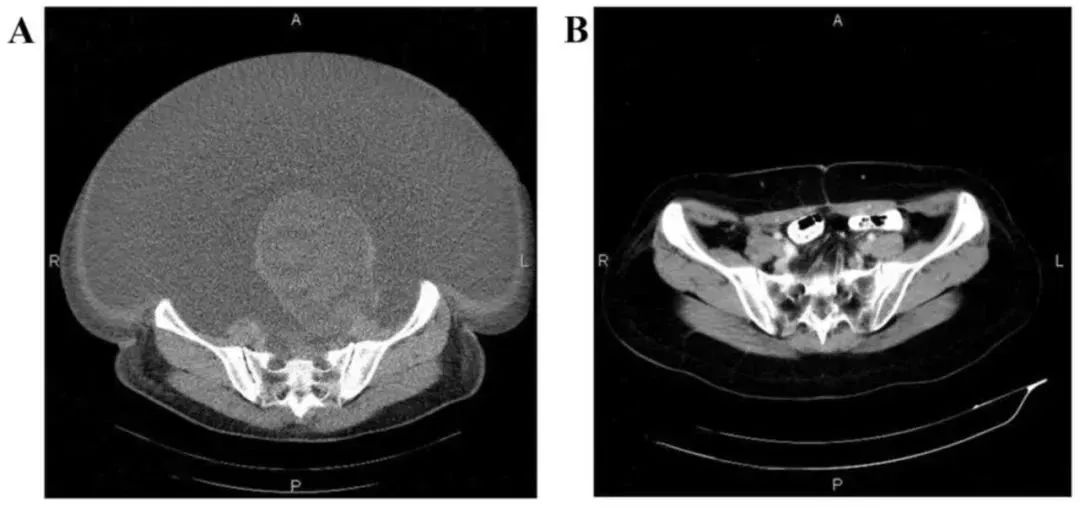

案例 2:国内一名 60 岁的卵巢癌晚期患者,在接受了体外扩增、高度活化的同种异体 NK 细胞的临床治疗后,CA125 水平从 11270 降至 580,所有腹水都消失了。此外,CT 扫描的肿块体积减小,并且没有出现副作用。 案例 3:一名广泛期小细胞肺癌患者,在进行 4 个疗程化疗和 4 次高度活化 NK 细胞临床干预后,患者第一次进行治疗后的 CT 复查结果显示,肿瘤缩小到了原来的 1/8。而且在距发病第六年的 CT 复查中,仍旧没有发现任何异常及复发的迹象。